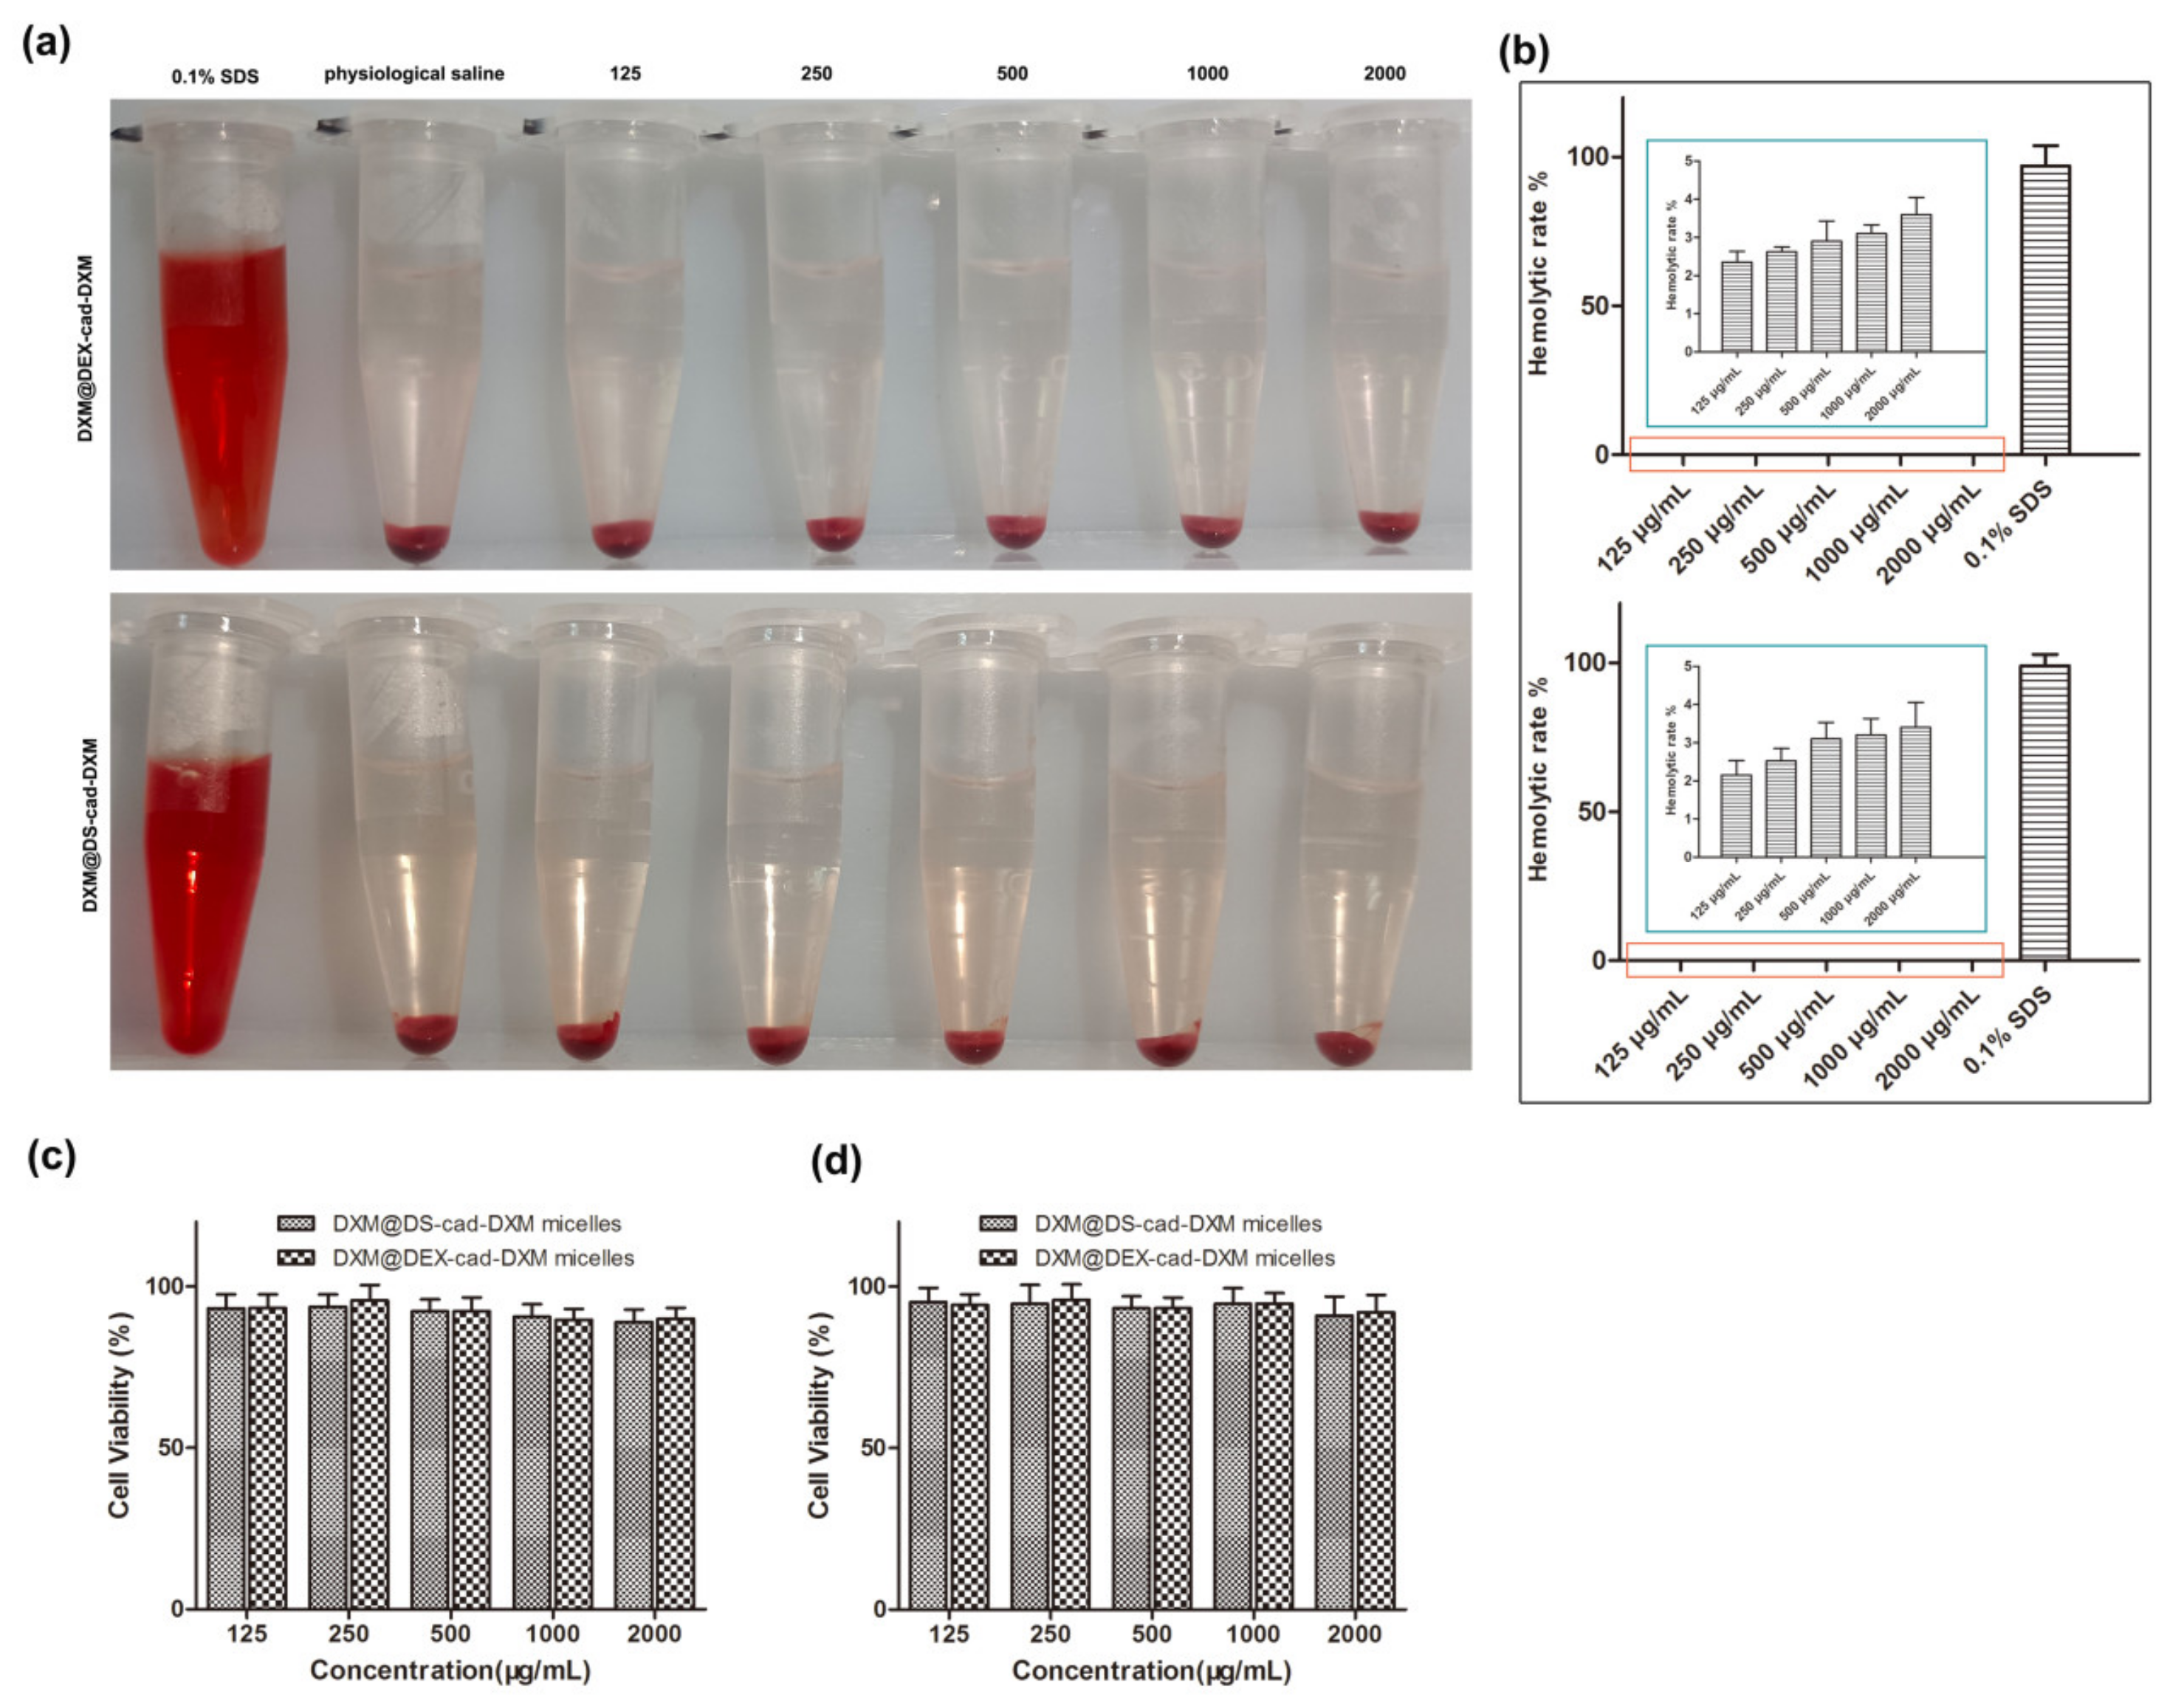

3.6. Biocompatibility Evaluation of DXM@DS-cad-DXM